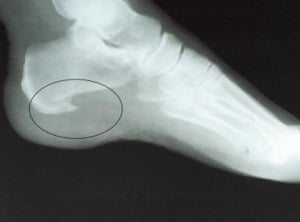

Как выглядит пяточная шпора: фото

На фото ниже показано, как проявляется заболевание у человека.

Пяточную шпору можно заподозрить на основании типичных жалоб на боли при ходьбе и осмотра стопы с прощупыванием пяточной кости. Но для подтверждения диагноза необходимо проведение:

- рентгена стопы с выявлением типичного нароста,